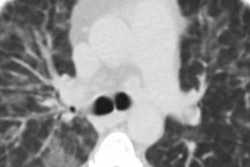

Response to cuff occlusion in the femoral circulation. A: Vessel-wall images of the superficial femoral artery (SFA) at different points (60 secs [A60], 90 secs [A90], and 120 secs [A120]) as indicated by crosses in B during reactive hyperemia. The dashed circles represent the lumen area at baseline. B: Superficial femoral vein (SFV) oxygen saturation (SvO2) at baseline (green line) and during hyperemia. C: SFA blood flow velocity (V). D: Axial image obtained with MRI in the thigh, with SFA and SFV indicated in red and blue, respectively. Δ SvO2 = peak-to-peak SvO2, HI = hyperemic index, PFR = peripheral flow reserve, RI = resistivity index, TFF = time of forward flow, TP = time to peak, TW = washout time, Vb = baseline velocity, VP = peak hyperemic velocity, Vr = retrograde velocity during early diastole, Vs = systolic velocity. Image courtesy of the RSNA.These findings suggest that vaping impairs the function of the endothelium. However, the researchers noted that more research is needed.